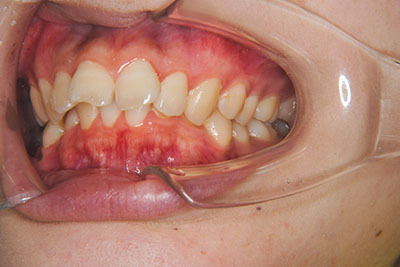

おとなの方でも矯正治療をあきらめないでください!

子供の頃に矯正治療を行う方が治療期間が短く済むというのは、確かですが、矯正治療は患者様の意識も重要です。

いくら歯が動き易くとも、本人がやる気でなければ効果は出ませんし、むし歯発生のリスクも高まります。おとなの方は顎の成長が終わっているため、治療の計画が立てやすいとも言えます。「もう大人だから…」とあきらめず、一度ご相談ください。